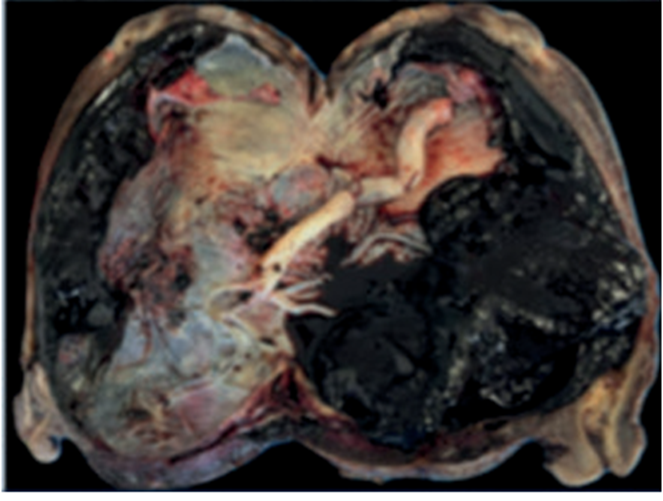

El diagnóstico de certeza fue anatomopatológico con la pieza de histerectomía, informando una placenta percreta, cuyas vellosidades penetran el espesor miometrial alcanzando y perforando la serosa uterina, con ausencia o mínimo endometrio decidualizado (figura 6).

El espectro de acretismo placentario se clasifica según el grado de invasión en: acreta, cuando las vellosidades coriónicas se adhieren al miometrio sin atravesar la decidua basal; increta, cuando las vellosidades penetran el miometrio, y, por último, la forma de mayor severidad, la placenta percreta, en donde las vellosidades traspasan el miometrio llegando a la serosa, incluso atravesándola hasta invadir órganos vecinos. A su vez, desde el punto de vista anatomopatológico puede clasificarse, según su extensión, en focal, parcial o total1.